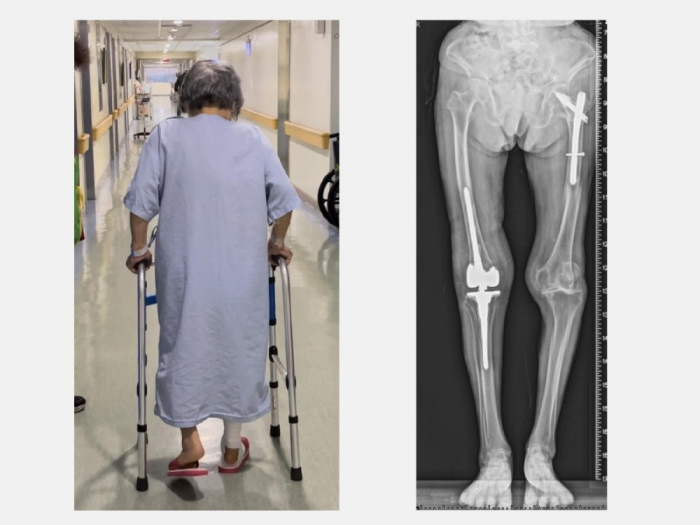

最後家屬經朋友介紹將老太太送到仁愛長庚合作聯盟醫院(大里仁愛醫院),在骨科部黃贊文部長的安排下,由骨科、復健科、麻醉科、心臟科、護理師和中醫師團隊的細心照護,順利完成人工膝關節再置換手術,老太太生日願望實現了,開心的走路出院,現在又可以騎腳踏車運動。

黃部長回憶門診當天的情形,老太太一臉沮喪由家屬推著輪椅來到門診,X光一看是人工膝關節旁的粉碎性骨折,由於年紀大骨質疏鬆嚴重,人工關節就像地基出現天坑一樣也整個鬆動。當天剛好是她的生日,痛苦了一個星期,生日願望只希望在餘生還能再站起來走路。

老太太手術當天下午就可以自己拿著助行器下床上廁所。此外,從手術隔天開始,除了骨質疏鬆症的治療,還搭配手術後疼痛中醫輔助醫療,復健科醫師也根據老太太的需求安排復健運動,在病床邊開始固定式腳踏車訓練。在手術後第5天,老太太開心的出院走路回家。